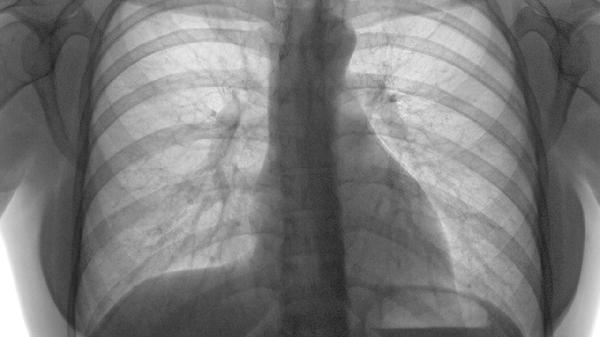

肋骨骨折合并右下肺肺不张可通过镇痛治疗、呼吸训练、物理治疗、手术治疗等方式干预。该情况通常由肋骨移位压迫肺组织、...

隐性肋骨骨折是指通过常规X线检查难以发现,但实际存在的肋骨骨折。 隐性肋骨骨折通常发生在肋骨受到外力作用但未完全...